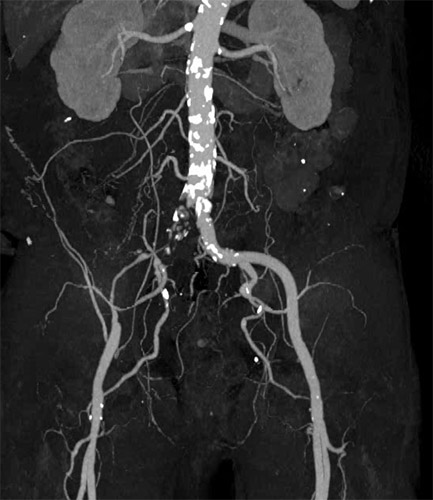

主訴は跛行(Rutherford分類3)の方で ABI検査を実施したところ0.62と低値。リスクファクターとして糖尿病(DM)、高血圧(HT)、脂質異常症(DL)が認められた。今回の標的病変は左大腿動脈(Lt. SFA CTO)【図1・図2】であり、アプローチ部位はTAI(Trans ankle intervention)にて施行することとした。

BKについてはATAは開存しており、PTAが途中から閉塞していることを確認した。【図3】